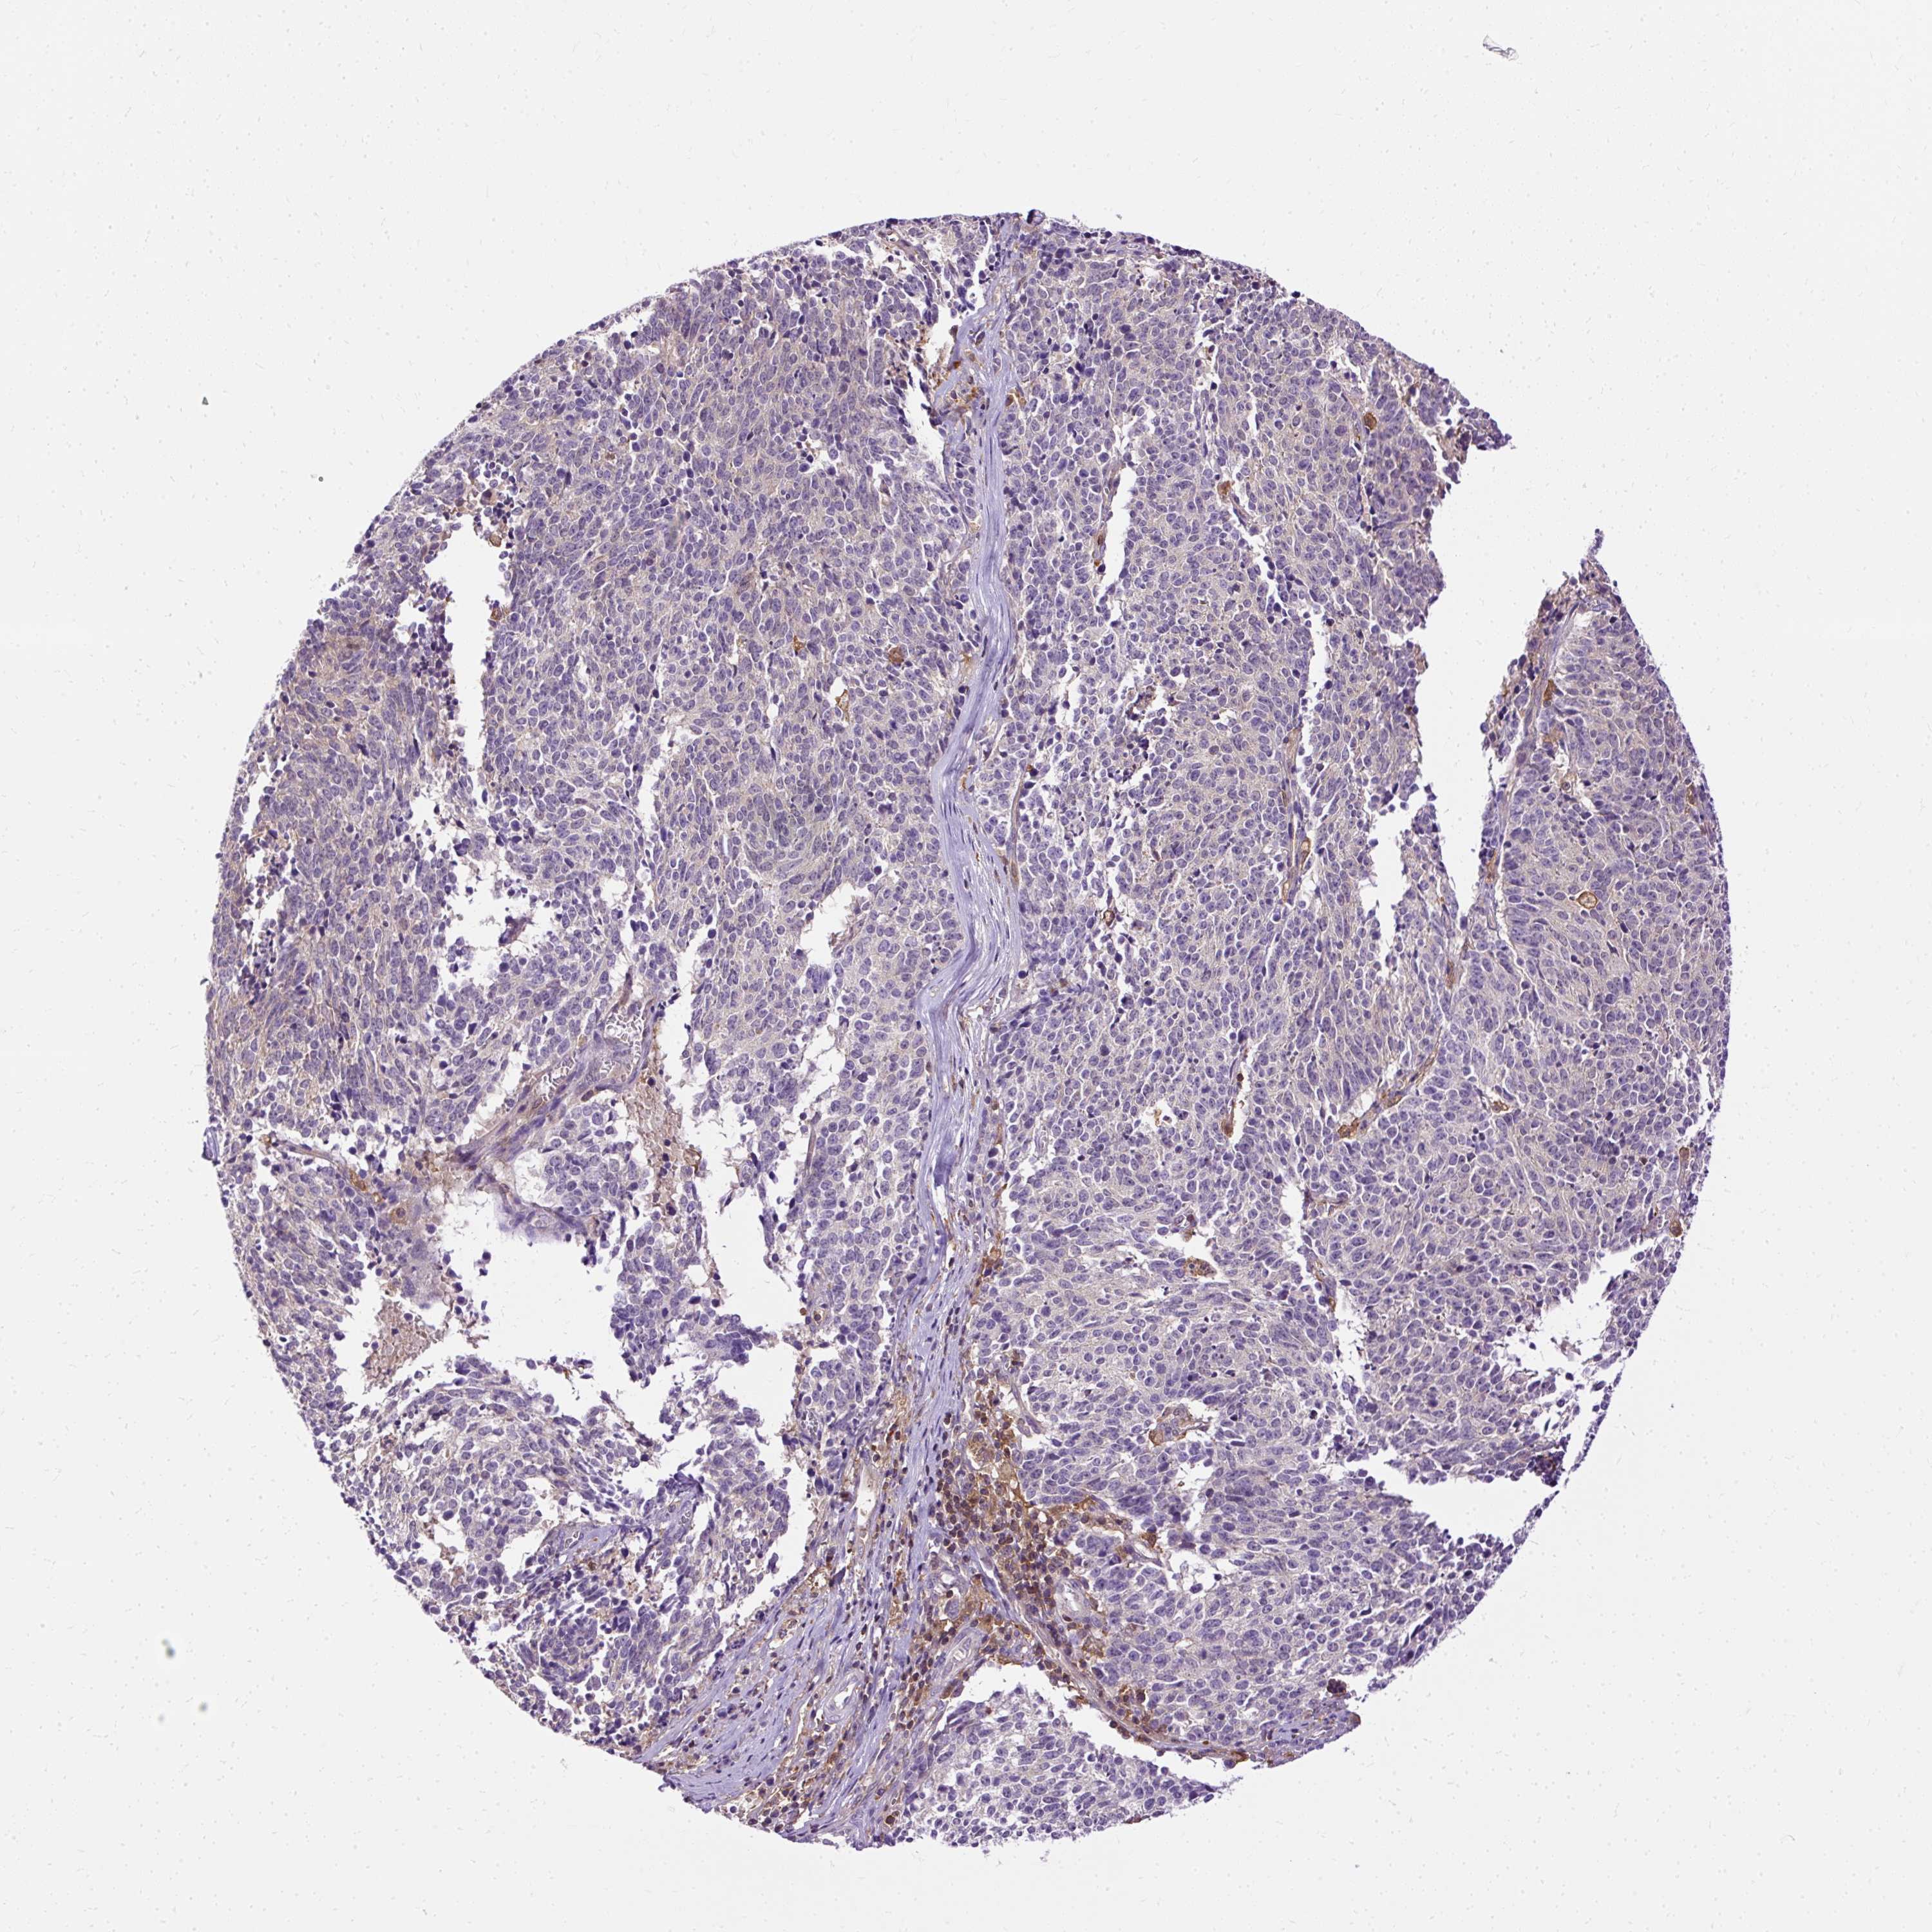

CERVICAL CANCER - Protein expressioni

A mouse-over function shows sample information and annotation data. Click on an image to view it in a full screen mode. Samples can be filtered based on level of antibody staining by selecting one or several of the following categories: high, medium, low and not detected. The assay and annotation is described here.

Note that samples used for immunohistochemistry by the Human Protein Atlas do not correspond to samples in the TCGA dataset.

Antibody stainingi

Antibody staining in the annotated cell types in the current human tissue is reported as not detected, low, medium, or high, based on conventional immunohistochemistry profiling in selected tissues. This score is based on the combination of the staining intensity and fraction of stained cells.

Each image is clickable and will lead to virtual microscopy that enables deeper exploration of all samples and also displays staining intensity scores, fraction scores and subcellular localization as well as patient and tissue information for each sample.

Antibody HPA053874

Staining

High

Medium

Low

Not detected

Intensity

Strong

Moderate

Weak

Negative

Quantity

>75%

75%-25%

<25%

None

Location

Nuclear

Cytoplasmic/membranous

Cytoplasmic/membranous,nuclear

Squamous cell carcinoma, NOS